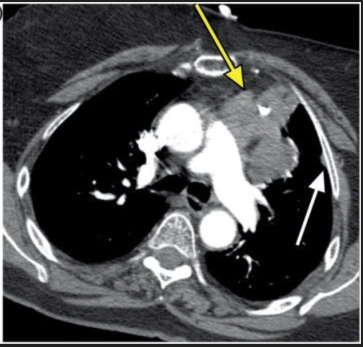

CT scan demonstrated a lobulated, left-sided anterior mediastinal mass (yellow arrow) and a 1-cm left-sided pleural nodule (white arrow).

A 67-year-old woman with a 6-year history of myasthenia gravis presents with worsening exertional dyspnea. Past medical history includes coronary artery disease (stent placement), diabetes, and intermittent shortness of breath with previous oxygen dependence due to MG. Family history is notable for a sister who died from myasthenia gravis complications. She has a 60 pack-year smoking history, quit 10 years ago. Diagnostic findings include a chest radiograph showing a lobulated anterior mediastinal mass with mild elevation of the left hemidiaphragm (suggestive of phrenic nerve involvement) and a CT chest revealing an 8-cm left-sided anterior mediastinal mass with a 1-cm left pleural nodule consistent with drop metastasis.